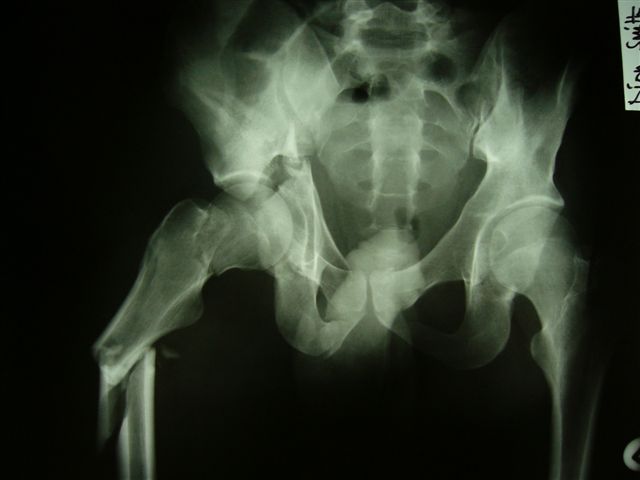

Anatoly F Lazarev 03 Сентябрь 2004, 22:18

Женя! Класный перелом. Отлично репонируется изнутри таза, но лучше фиксированть сзади. Классический перелом для двустороннего доступа.

Однако есть альтернатива. Репозиция из подвздошного доступа тазовыми щипцами с разнодлинными браншами или тазовым пистолетом, а фиксация задней колонны через седалищный бугор или тазрвыми винтами 4,5 или каннюлированными 6,5 или 7,3. По-моему я посылал на ортофорум такой снимок, когда жаловался на ишемический неврит седалищного нерва через сутки после операции. Не забудь про шейку бедра - мне кажется будет хорош длинный PFN любой фирмы, какую ты найдешь, а нет так UFN + miss a nail, как это здорово делают мои земляки - Ебурбуки. Пока.

Anatoly F Lazarev 03 Сентябрь 2004, 22:39

Высылаю пример еще одного случая, остеосинтез пластиной из подвздошного доступа.